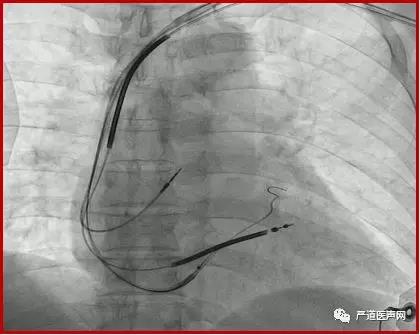

Metronic 4296 双阴极电极,6248辅助鞘

手术过程